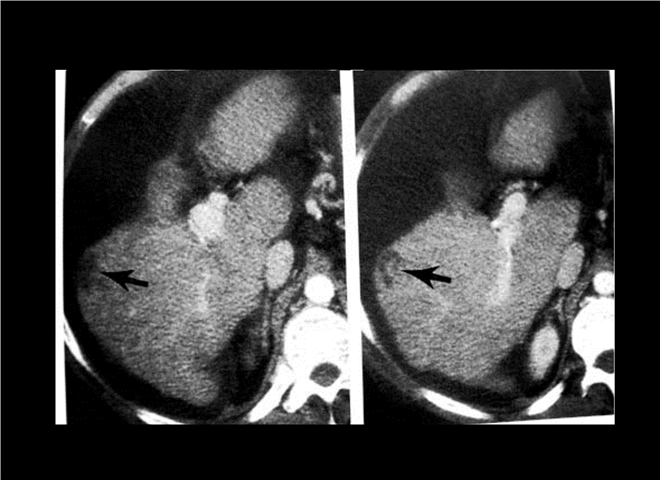

13_CT增强扫描